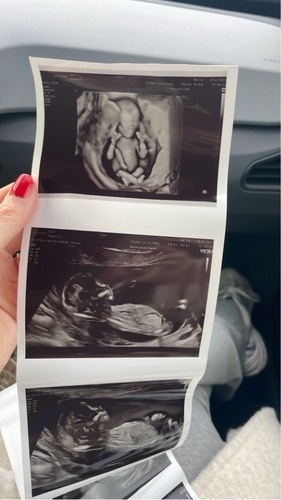

Echo met 12 weken, wat denken jullie? Met 11 weken dacht ik duidelijk een nub te zien wat dan een meisje zou zijn, maar deze zie ik het niet 🙈

Wat denken jullie?

Wauw wat een mooie echo die bovenste! Ik denk een meisje.